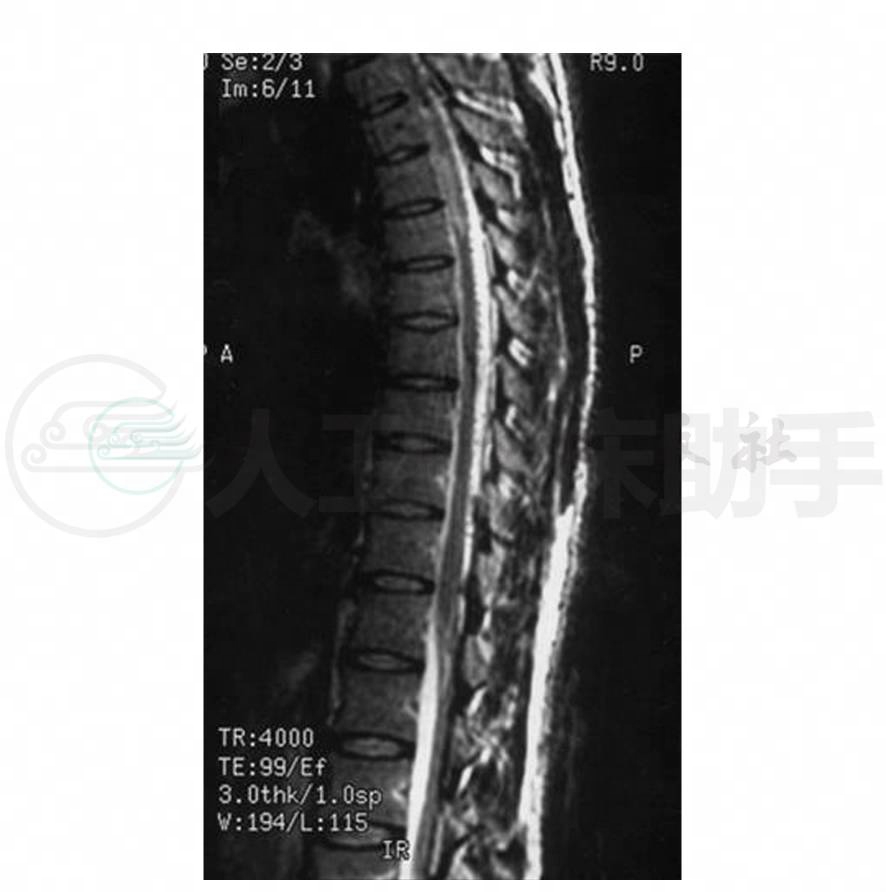

8.胸椎MRI(1998-12-25)胸3以下脊髓稍增粗,脊髓内呈T1WI稍低、T2WI高信号,边缘模糊,脊髓与蛛网膜间不规则,椎管无明显狭窄,椎体大小,形态及附件未见异常改变(图1,图2)。增强扫描(1999-1-8)示“上述病灶略有增强,考虑胸段脊髓之改变以脊髓炎可能性大,不除外星形细胞瘤”。

图1 胸椎MRI矢状位T1WI示胸3以下脊髓稍增粗,脊髓内异常稍低信号,边缘模糊